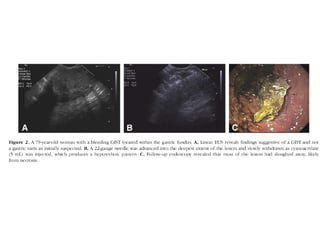

Injection Therapy

Tumor Therapy

Alcohol Injection into a Mediastinal Metastasis compressing the Esophagus